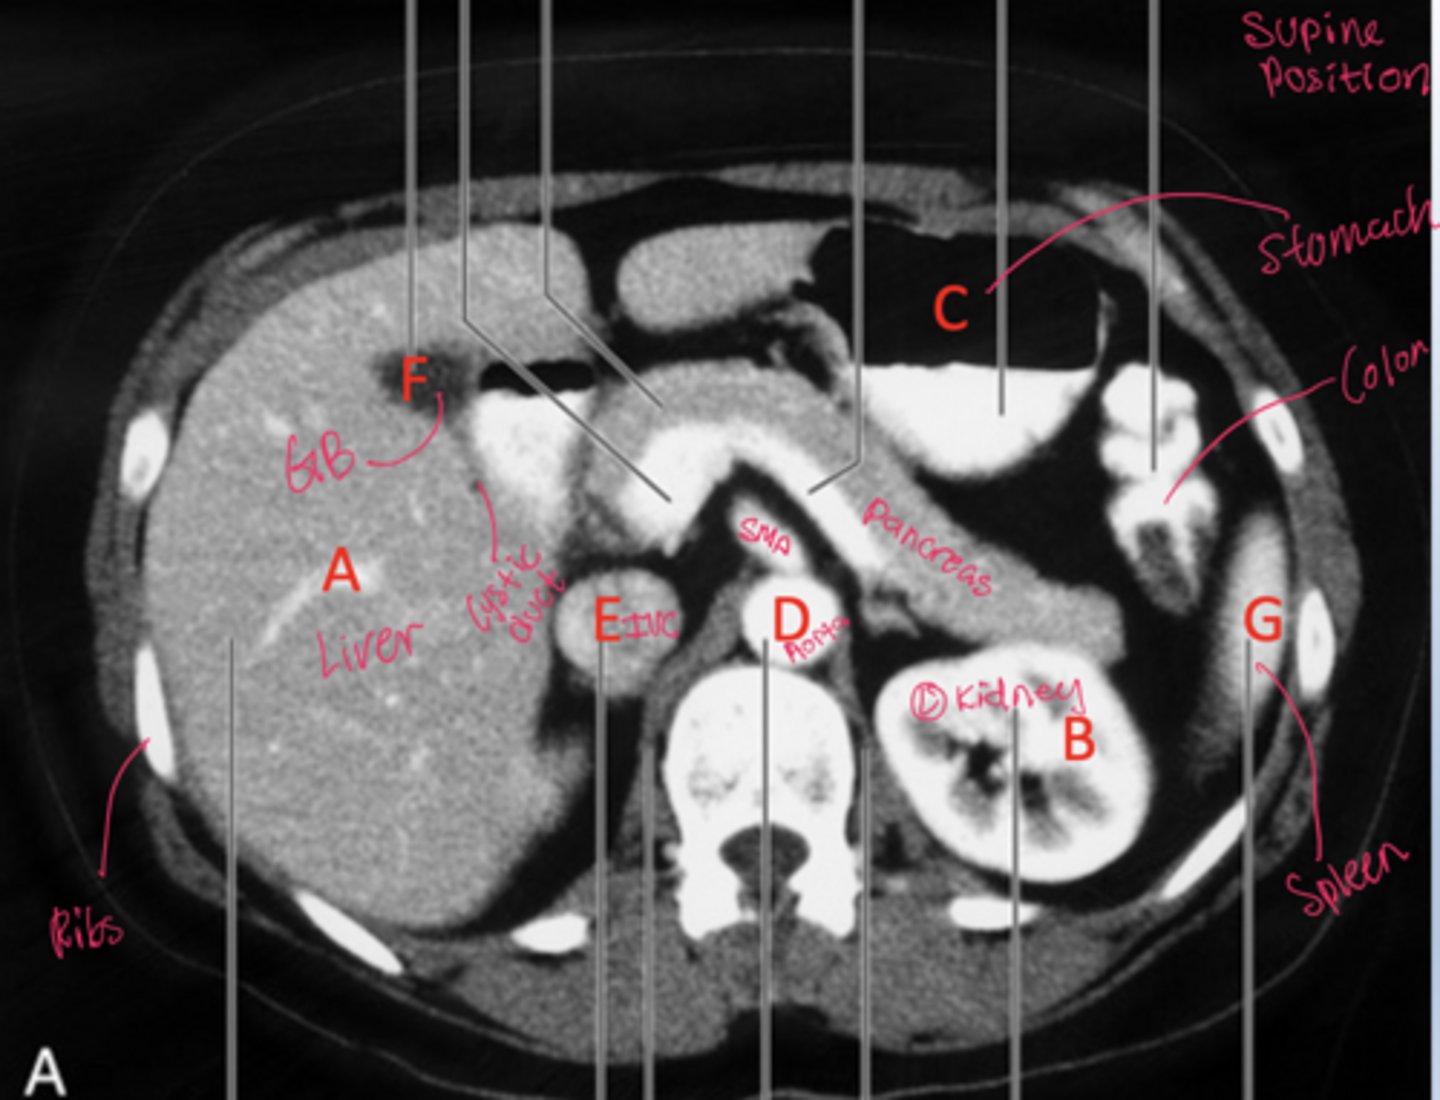

Be able to label the radiograph

How can patient position on CT be determined using fluid and air distribution?

Fluid moves to the dependent (lowest) side, while air rises to the non-dependent (highest) side due to gravity

Where do fluid and air collect on CT when a patient is supine?

Fluid collects posteriorly (toward the back) and air collects anteriorly.